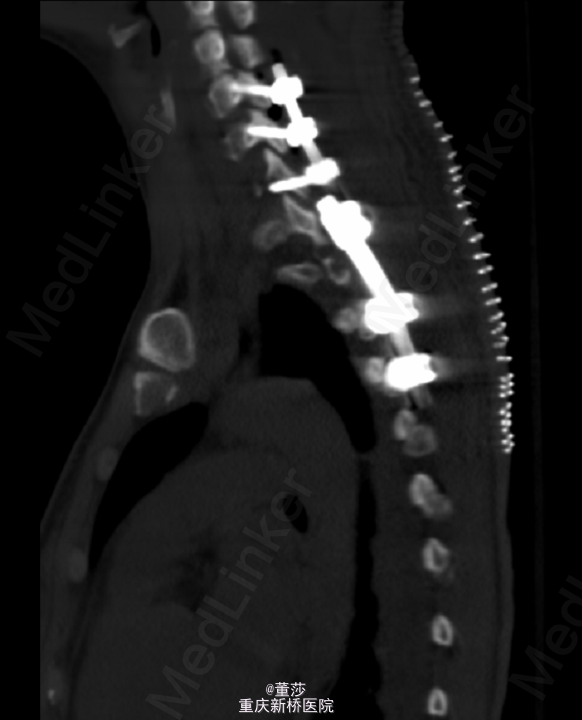

初步诊断:1.胸椎肿瘤:转移癌/肺恶性肿瘤。全身麻醉下行“胸椎恶性肿瘤后路肿瘤切除,椎管减压、内固定术”,术中予椎体内填充骨水泥,C5,C6,C7各打入一枚颈椎侧块螺钉,T3、T4两侧各打入一枚椎弓根螺钉,C臂机透视提示螺钉位置可。

术中冰冻:胸1,2椎肿瘤(2):显著增生的纤维结缔组织内有少量异型细胞,考虑转移性低分化腺癌。术后予锋替新2.0g ivgtt bid预防感染及镇痛,补液改善循环,促进愈合治疗等对症治疗。术后复查胸椎片:颈、胸椎后路术改变,术后内固定在位,胸1、2椎体内见高密度影。胸椎顺列。所见椎间隙无殊。